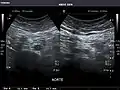

Liver

Ultrasonography of the liver with some standard measurements[6]

In patients with deranged liver function tests, ultrasound may show increased liver size (hepatomegaly), increased reflectiveness (which might, for example, indicate cholestasis), gallbladder or bile duct diseases, or a tumor in the liver.

Ultrasonography of liver tumors involves two stages: detection and characterization. Tumor detection is based on the performance of the method and should include morphometric information (three axes dimensions, volume) and topographic information (number, location specifying liver segment and lobe/lobes). The specification of these data is important for staging liver tumors and prognosis. Tumor characterization is a complex process based on a sum of criteria leading towards tumor nature definition. Often, other diagnostic procedures, especially interventional ones, are no longer necessary. Tumor characterization using the ultrasound method will be based on the following elements: consistency (solid, liquid, mixed), echogenicity, structure appearance (homogeneous or heterogeneous), delineation from adjacent liver parenchyma (capsular, imprecise), elasticity, posterior acoustic enhancement effect, the relation with neighboring organs or structures (displacement, invasion), vasculature (presence and characteristics on Doppler ultrasonography and contrast-enhanced ultrasound (CEUS).